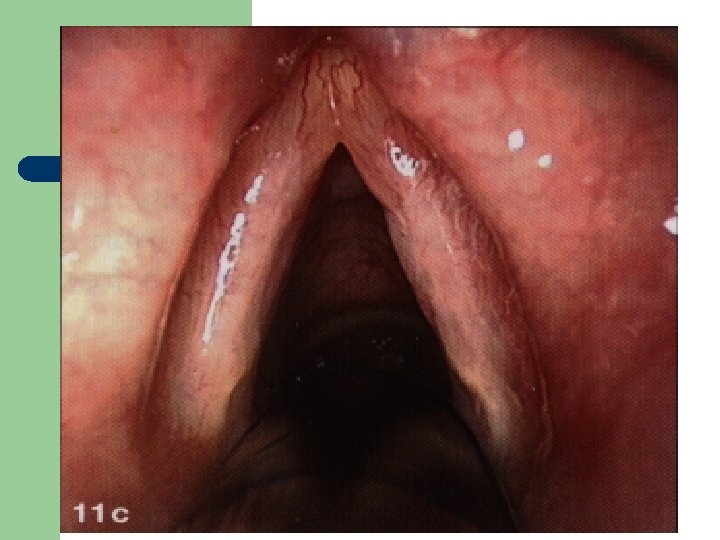

Vývoj dětské chraptivosti l 1. 2. 3. 4. Průvodním jevem při dětské chraptivosti je pokašlávání a pochrchlávání. Nález na hlasivkách postupuje takto: Hyperemické (překrvené hlasivky, Hypertrofické, vřetenovité zduření, hlasivkový uzávěr je neúplný a hlas má dyšnou příměs, ventrikulární řasy se začínají vyklenovat Zpěvácké uzlíčky, nejčastěji na hranicích přední a střední třetiny hlasivek Atrofie hlasivek až s podélnou rýhou, při fonaci nedomykavost uzávěru.

Hlasivkový uzlík l

Hlasivkový uzlík l

Hlasivkové uzlíky l